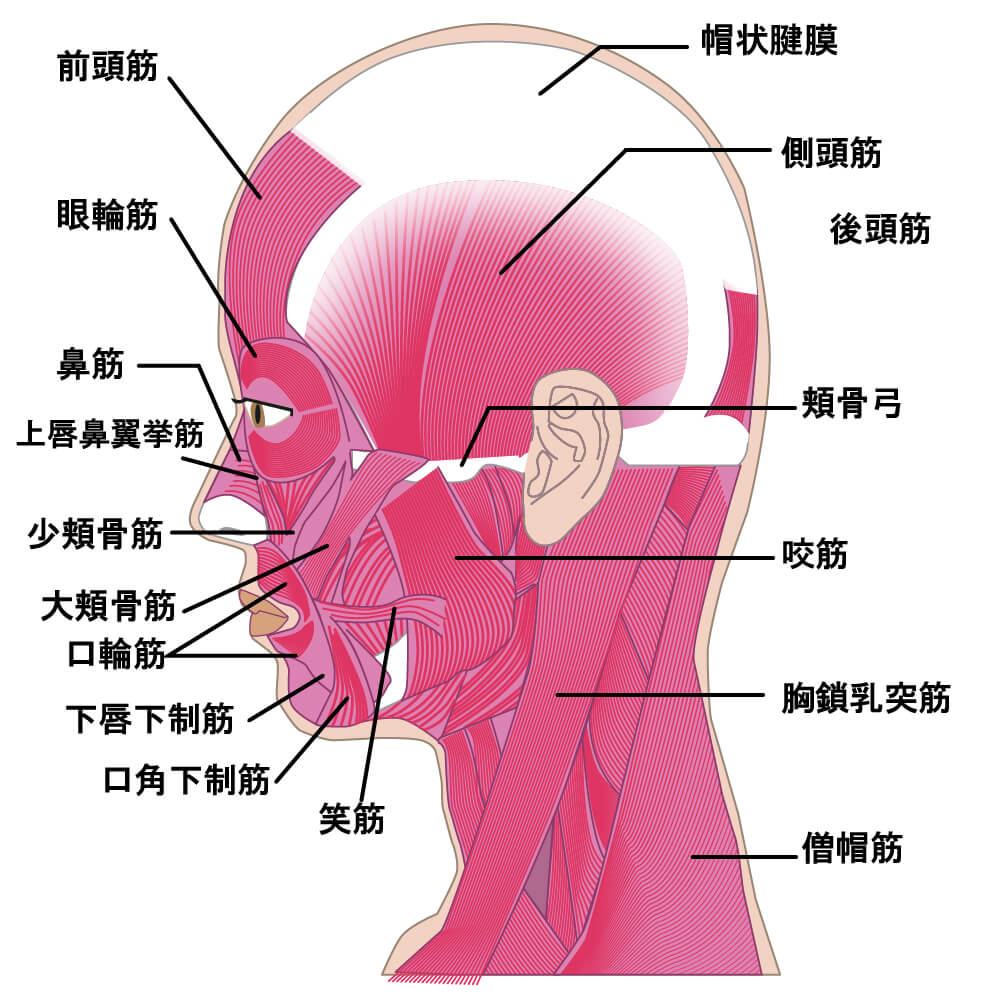

筋膜とは何か?

筋膜とは、筋肉を包む薄い膜のこと。

鶏肉をさばいたことがある方は、薄い透明の皮のようなものを見たことがあるかもしれません。

あれが「筋膜」です。

この膜は、筋肉の形を保ったり、他の組織と滑らかに動くようにサポートする役割を持っています。

よくあるのは、肩甲骨の内側や腱鞘炎を起こしやすい前腕の筋膜です。